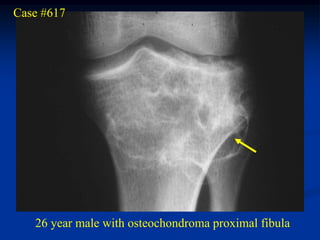

Case #617

26 year male with osteochondroma proximal fibula

Lateral view